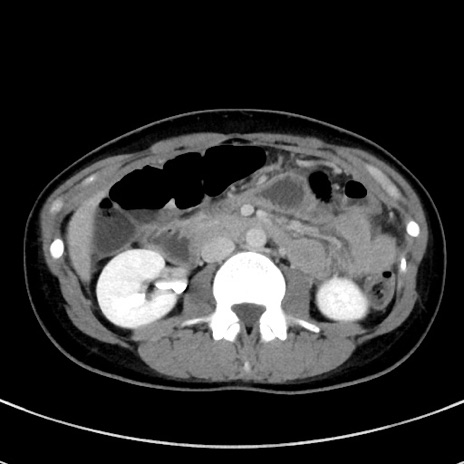

症例17(横断像)

【症例】20歳代女性

【主訴】嘔吐、下腹部痛

【現病歴】昨日夕食後に嘔吐し下腹部痛が出現。本日になっても嘔吐持続し改善しないため来院。

【身体所見】意識清明、BT 37.2℃、BP 108/67mmHg、腹部:平坦、やや硬、下腹部正中から右にかけて圧痛あり、反跳痛軽度あり、tapping pain(+)。

【データ】WBC 13600、CRP 14.94